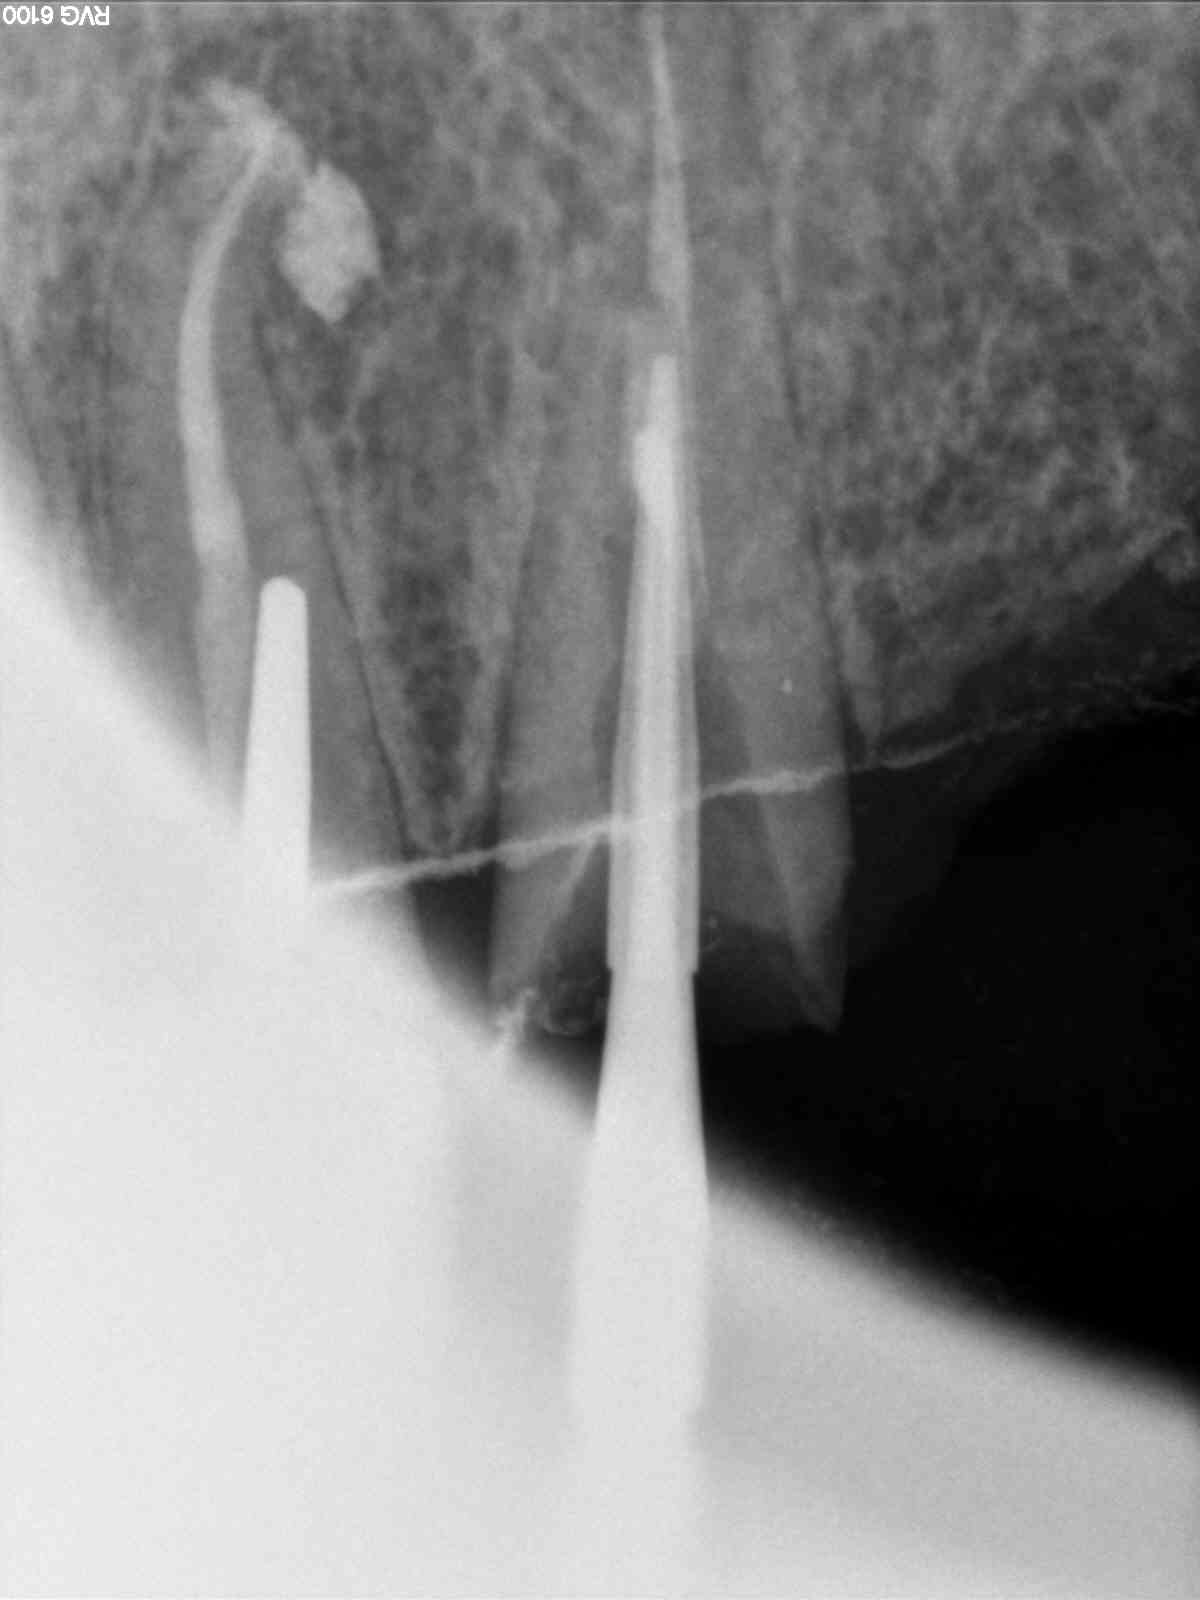

Bridge 41 31 32 33.....

Gouré de ciment de scellement. Utilisé du luxacore à la place. Impossible de sceller inlay core de 33 c'était pris. -)

La radio c'est à quel moment? Après ou avant d'avoir essayé de virer le luxacore?

A priori t'es pas dans l'axe..... parti de travers en essayant d'éliminer le mauvais ciment?

J'essaierai fraise boule acier col long petit diametre sur contre angle bleu ou vert pour creuser dans le residu au fond, retrouver la lumiere canalaire et essayer de recuperer l'axe pour refaire i core.

Viens de retourner voir image jointe.... le moignon est me semble-t-il félé, on voit une ligne sombre quart inferieur gauche de l'image qui semble démarrer à peripherie de la preparation et descendre jusque dans la lumière canalaire...

Après évidemment. Mais je ne suis pas joueur au point de continuer à essayer de virer le reste. .

C'est ca sauf que ca ne semble pas etre de travers. J'ai bien essayé de rectifier le tir mais quand ca veut pas ca veut pas. J'ai pas envie de foirer dans le sens vestibulo lingual en plus si ca n'est déjà fait. Il y a assez de dégâts comme ca. -)

D'après ce qu'on voit sur les Rx j'irais quand même bien enfouir les limites, histoire de cercler au max, il y a de la rétention sur ton IC ? Et les forces vont se répartir d'une drôle de façon sur ton IC et dans le canal :(

Je voyais comme algi une solution de continuité entre racine et le coronaire, sans doute ta reconstitution pré endo, qui peut un peu te gener peut etre pour trouver ton bon axe.